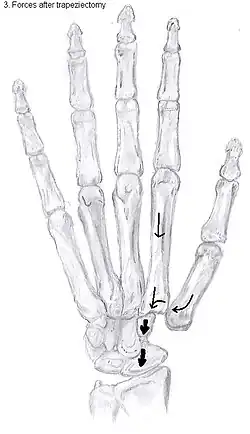

Trapeziectomy

During trapeziectomy,[30] the trapezium bone is removed without any further surgical adjustments. The trapezium bone is removed through an approximately three centimeter long incision along the lateral side of the thumb. To preserve surrounding structures, the trapezium bone is removed "by splitting" it into pieces.

An empty gap is left by the trapeziectomy and the wound is closed with sutures. Despite this gap, no significant changes in function of the thumb are reported.[27] After the surgery, the thumb will be immobilized with a cast.

Trapeziectomy with tendon interposition

Some physicians still believe that it is better to fill the gap left by the trapeziectomy. They assume that filling the gap with a part of a tendon is preferable in terms of function, stability and position of the thumb. This is based on the assumption that interposition can help maintain the space between the metacarpal and the scaphoid, which will improve comfort and capability. Neither of these assumptions is supported by experimental evidence.

Trapeziectomy with ligament reconstruction

Another technique is used to reconstruct the volar beak ligament after trapeziectomy. The rationale is that ligament reconstruction(LR) helps maintain the gap between the metacarpal and the scaphoid, and that a larger gap is associated with greater comfort and capability.[32] Again these possibilities are not supported by experimental evidence.

Trapeziectomy with LRTI

Some physicians believe that combining LR with TI will help maintain gap between the metacarpal and the scaphoid.[33] And that doing so will improve comfort and capability. Keep in mind that these aspects of the rationale are not supported by experimental evidence. The evidence suggests that all of these procedures have comparable long-term results.